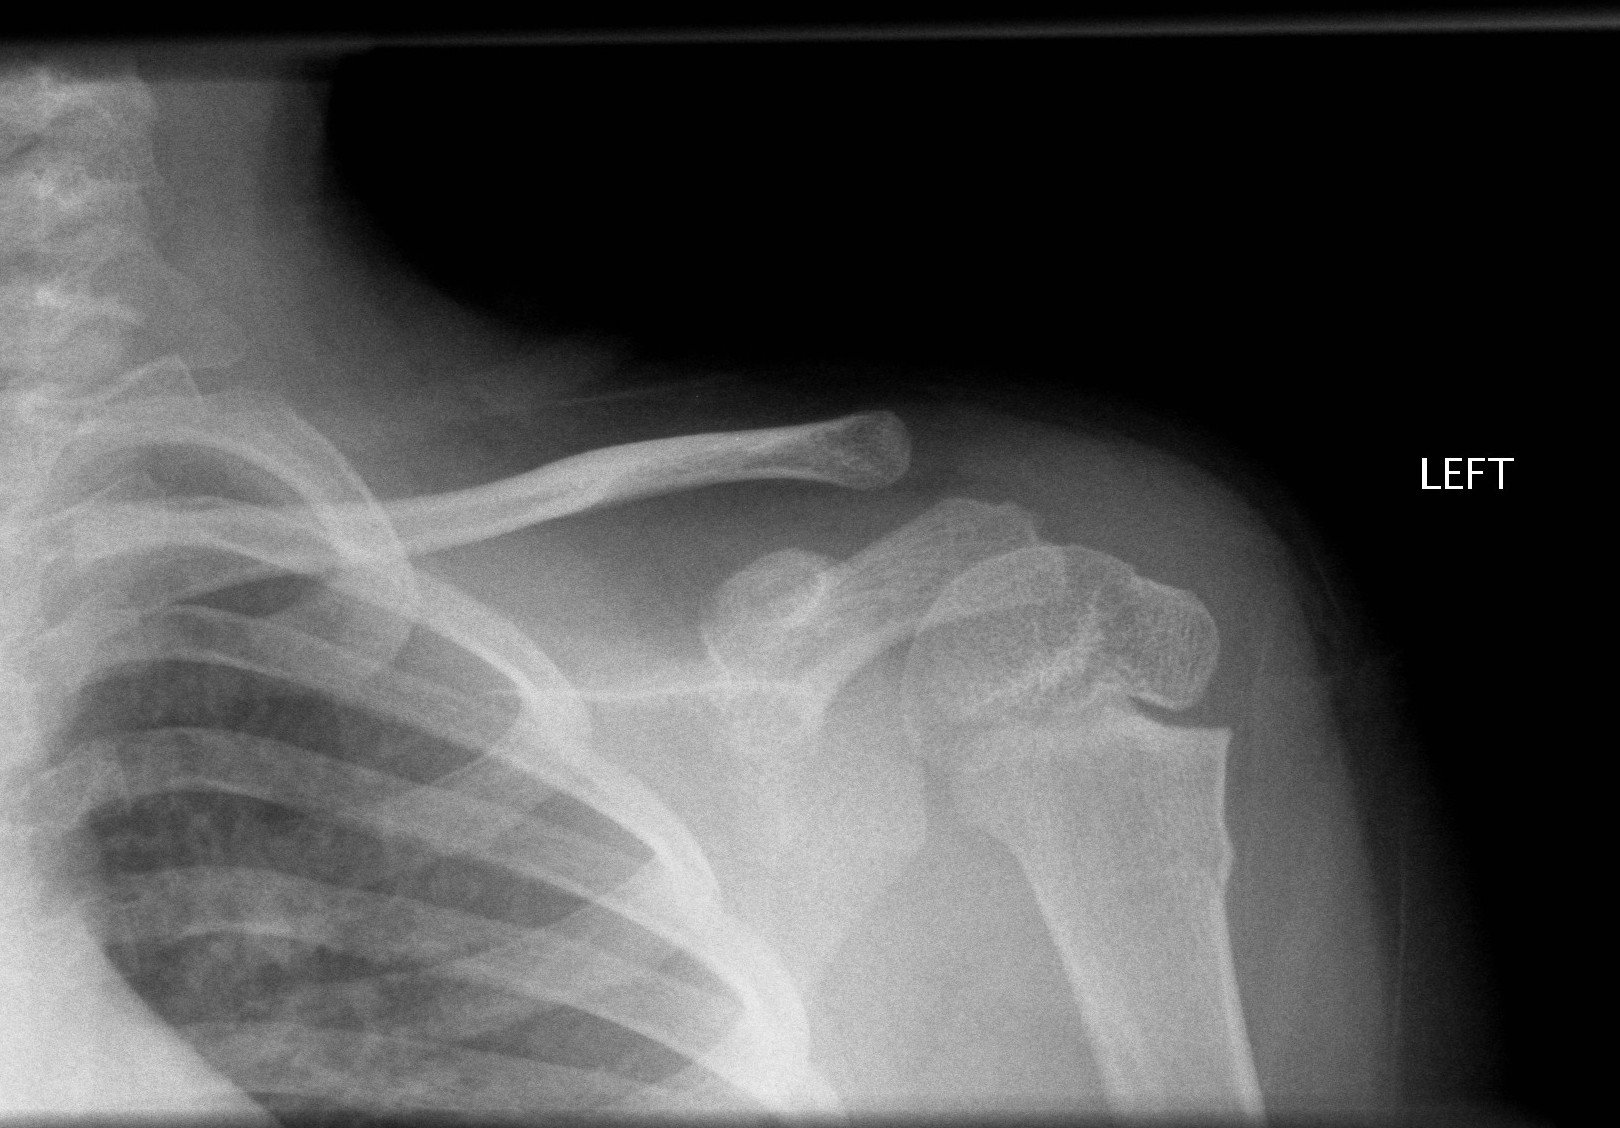

Above: Buckle fracture of proximal humerus

Above: Proximal humerus fracture with 40 degrees of angulation

Above: Salter-Harris II fracture of proximal humerus